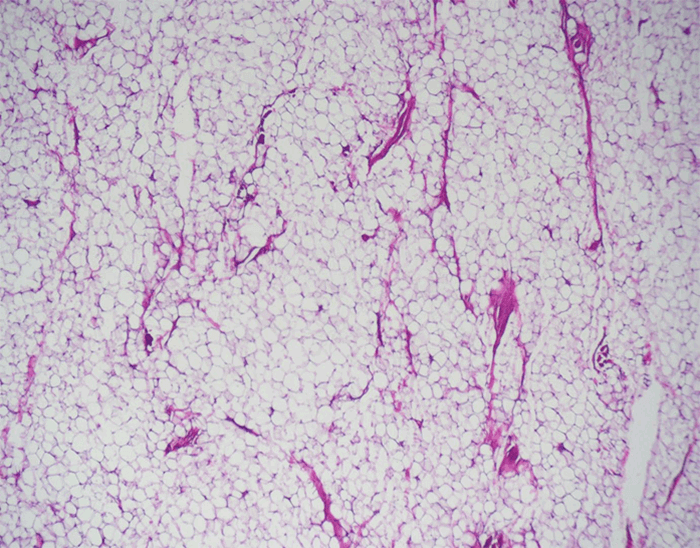

A 61-year-old, right-hand-dominant female was seen in the clinic for a five-year history of a left middle finger mass. The patient had complaints of mild tenderness directly over the mass, no distal paresthesia, and full range of motion with mild mass impingement at full flexion. Examination revealed a soft, well-circumscribed mobile mass involving the volar aspect of the middle finger with normal appearing skin overlying it (Figure 1A). The mass was confined to the proximal phalanx but did extend dorsally along the radial and ulnar side of the finger. Magnetic resonance imaging (MRI) was consistent with lipoma, revealing a homogenous, multi-lobular encapsulated mass 2.5 by 3.5 cm in size (Figure 1B). The patient was taken to the OR for excision through a Bruner incision. Notably, the mass had grown between the digital neurovascular bundle, separating the digital nerve from proper digital artery (Figure 1C and Figure 1D). The artery remained dorsal to the neoplastic growth, while the nerve had been forced toward the volar portion of the finger. Pathology of the specimen revealed numerous mature adipocytes, confirming the rare diagnosis of digital lipoma (Figure 2A). Postoperatively, the patient did well and healed completely. She achieved painless, full range of motion along with normal sensibility.

Figure 2. Pathology section of digital lipoma. Mature adipocytes are present throughout the visual field with uniform nuclei confirming the diagnosis of digital lipoma.